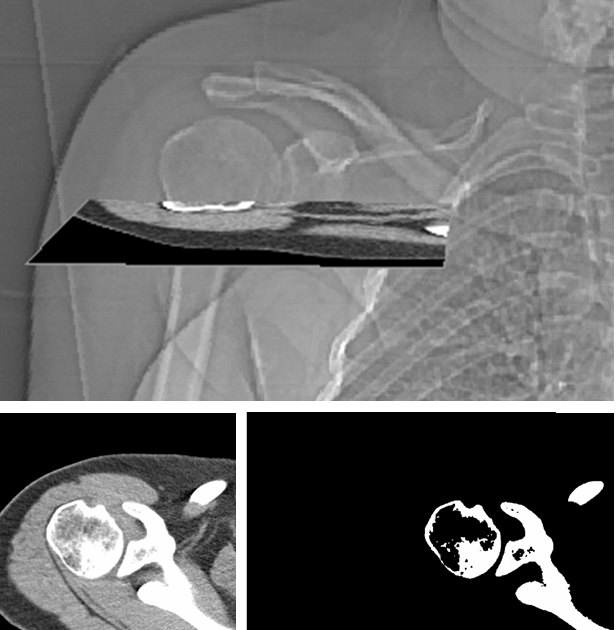

Uk snomed ct clinical edition nhs data migration april 2020. Biceps tendinitis is a disorder of the tendon around the long head of the biceps muscle. Bicipital groove segmentation from ct data. Ct scan methods accurately measure humeral head retroversion while radiographic methods do not.

The ct scan method and the computer assisted method enabled measurement of the distance between the central axis of the humeral head defined as the center of rotation of the humeral head articular surface and the posterior margin of the bicipital groove as performed by tillet et al. This was performed on 20 humeri ie 10 pairs to allow. Inflammation of the biceps tendon within the intertubercular bicipital groove is called primary biceps. We also assessed the distance between the humeral head central axis and the bicipital groove.

Bicipital groove x ray see more descriptions. This tool allows you to. In this project we investigate the relationship between the 3d shape of the bicipital groove and the incidence of pathology of the long biceps tendon. Two views of a humeral head extracted from mri with the bicipital groove indicated.

Bicipital groove segmentation from ct data. Bicipital groove x ray bicipital groove x ray procedure hide descriptions. Two views of a humeral head extracted from mri with the bicipital groove indicated. The biceps tendon is contained in the rotator interval a triangular area between the subscapularis and supraspinatus tendons at the shoulder figure 1.